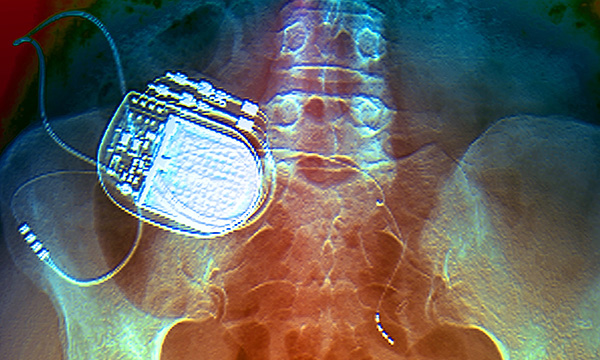

Bioelectrical medicine gives practitioners a fresh outlook on the treatment of chronic pain, finds a study that reviewed stimulation of the spinal cord, dorsal root ganglion and peripheral nerves